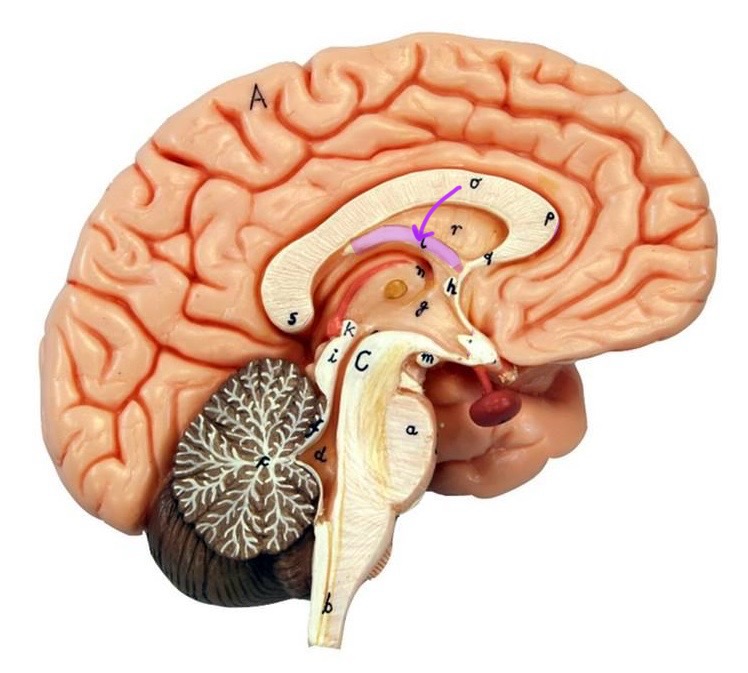

What is D?

lateral ventricle

Imagine thin membrane separating the 2 lateral ventricles

septum pellucidum

What is C?

3rd ventricle

What is B?

cerebral aqueduct

What is A?

4th ventricle

What is below A at the very end?

central canal (spinal cord)

What is C?

midbrain

tectum (corpora quadrigemina): superior colliculus

tectum (corpora quadrigemina): inferior colliculus

What is a?

pons

medulla oblongata

intermediate mass of thalamus

hypothalamus

What is the pink bulb?

pineal gland

corpus callosum

fornix

What is A?

cerebral cortex

cerebral tracts

cerebral hemispheres

longitudinal fissure

What are these ridges?

gyri

What are these shallow grooves?

sulci

Divides parietal from frontal lobe

central sulcus

precentral gyrus

postcentral gyrus